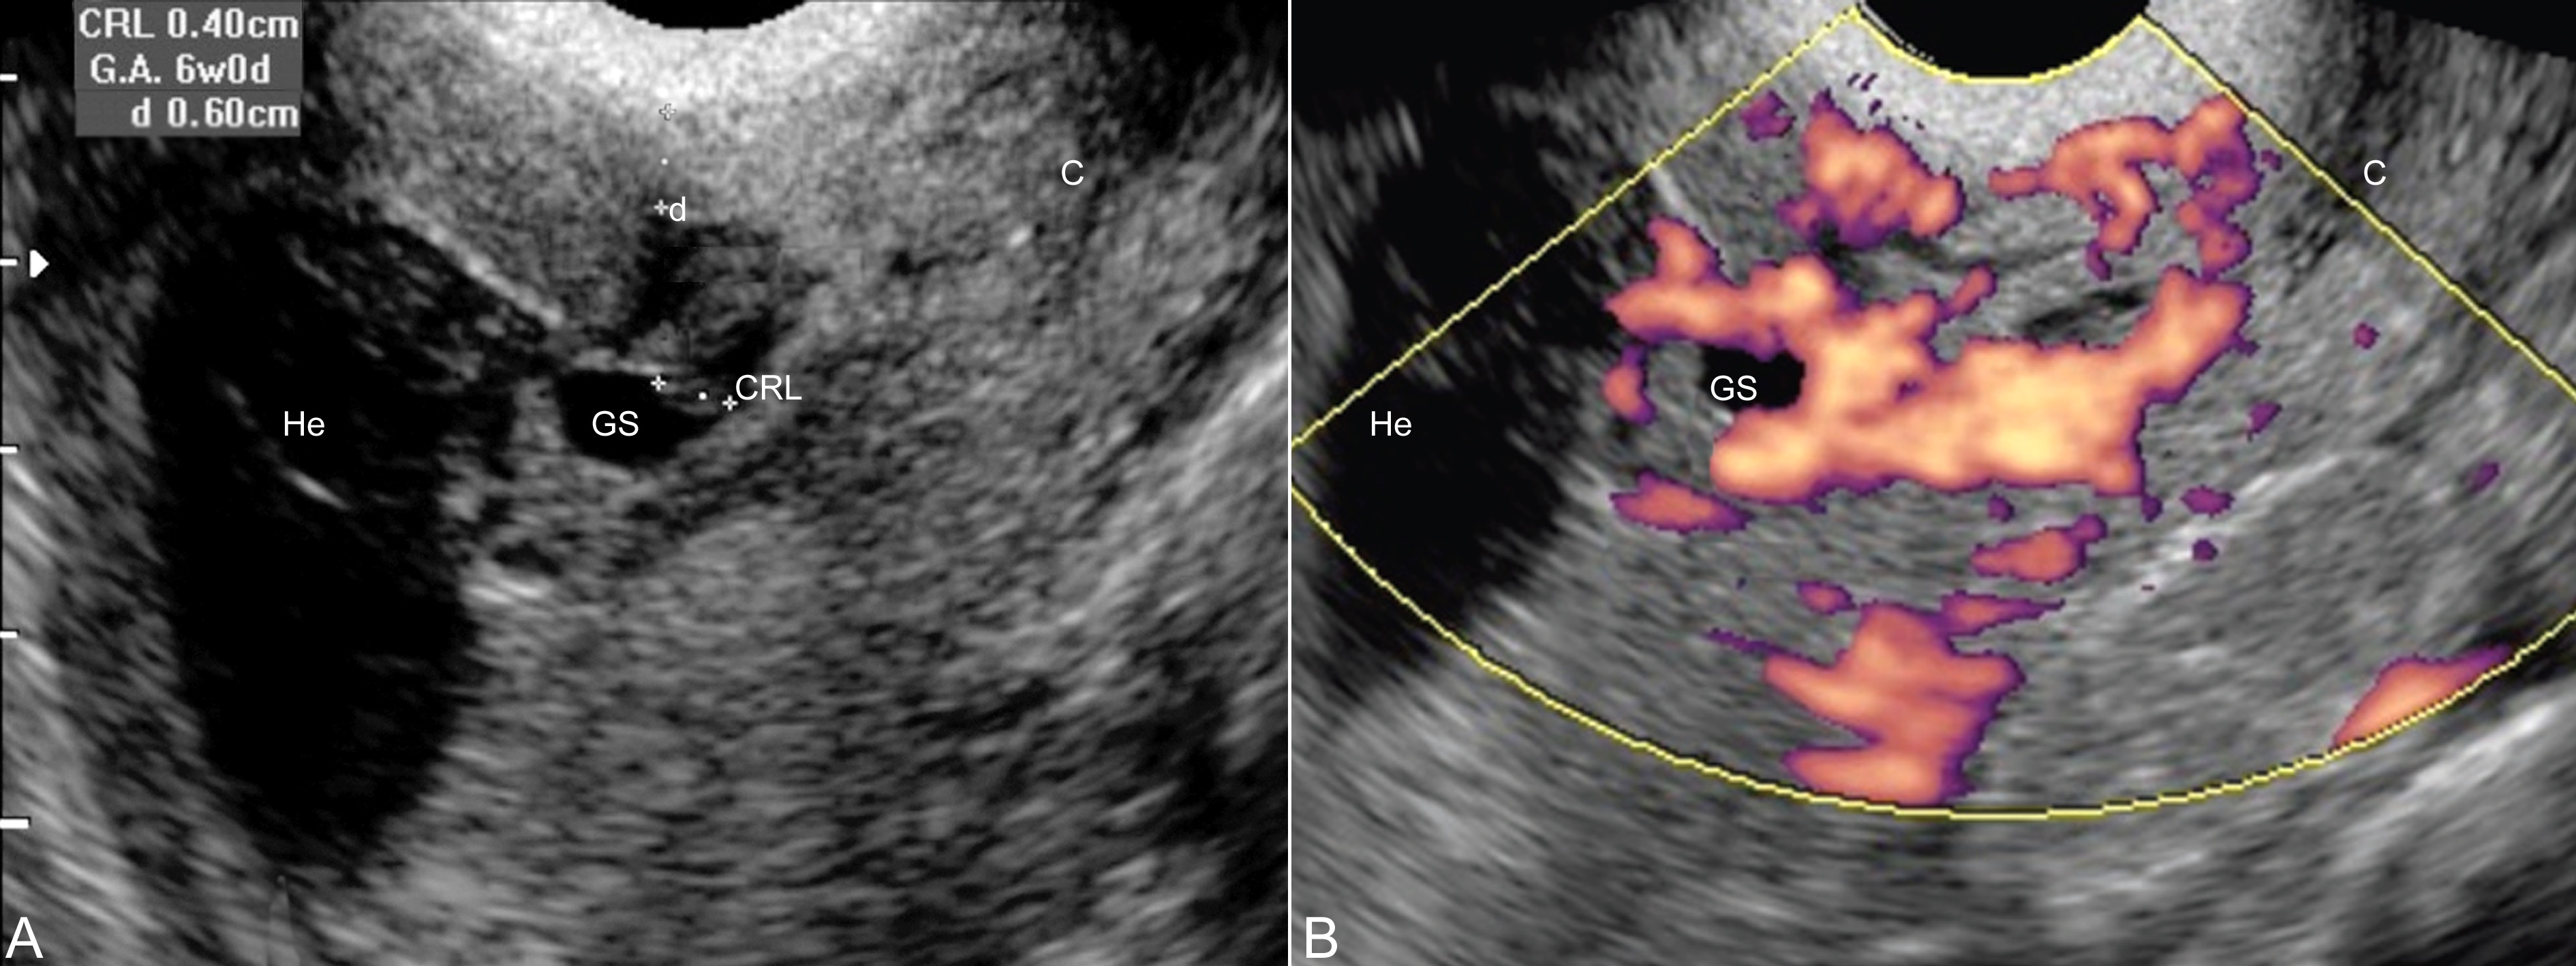

图2子宫瘢痕处妊娠并宫腔积血

A:二维超声瘢痕处子宫壁厚度6mm,局部可见孕囊(GS)显示,胚胎CRL4mm,宫腔内显示积血(He),宫颈(C)未见异常

B:能量多普勒超声检查显示瘢痕处孕囊(GS)周围血流增多显示,宫腔内显示积血(He),宫颈(C)未见异常